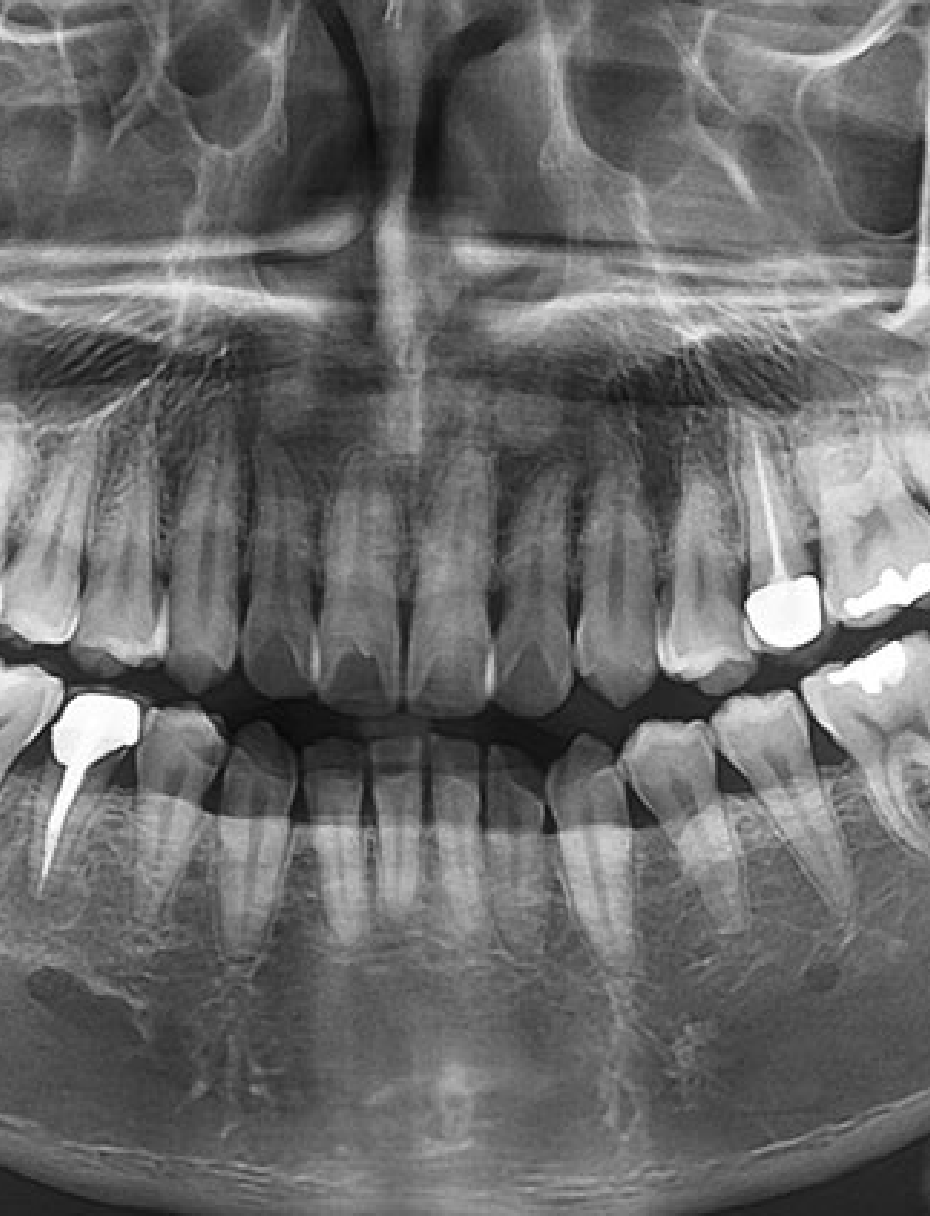

La radiologie dentaire 3D est devenue une alliée incontournable pour le diagnostic et la planification des soins complexes. Avec notre gamme de panoramiques numériques, vous accédez à une imagerie haute définition en quelques secondes, tout en réduisant les doses d’exposition pour le patient.

Jusqu’à 90 µm de précision pour des diagnostics cliniques sûrs.

Adaptez le champ de vision (FOV) à chaque indication clinique.

Pour planifier et sécuriser vos chirurgies grâce à des coupes 3D précises.